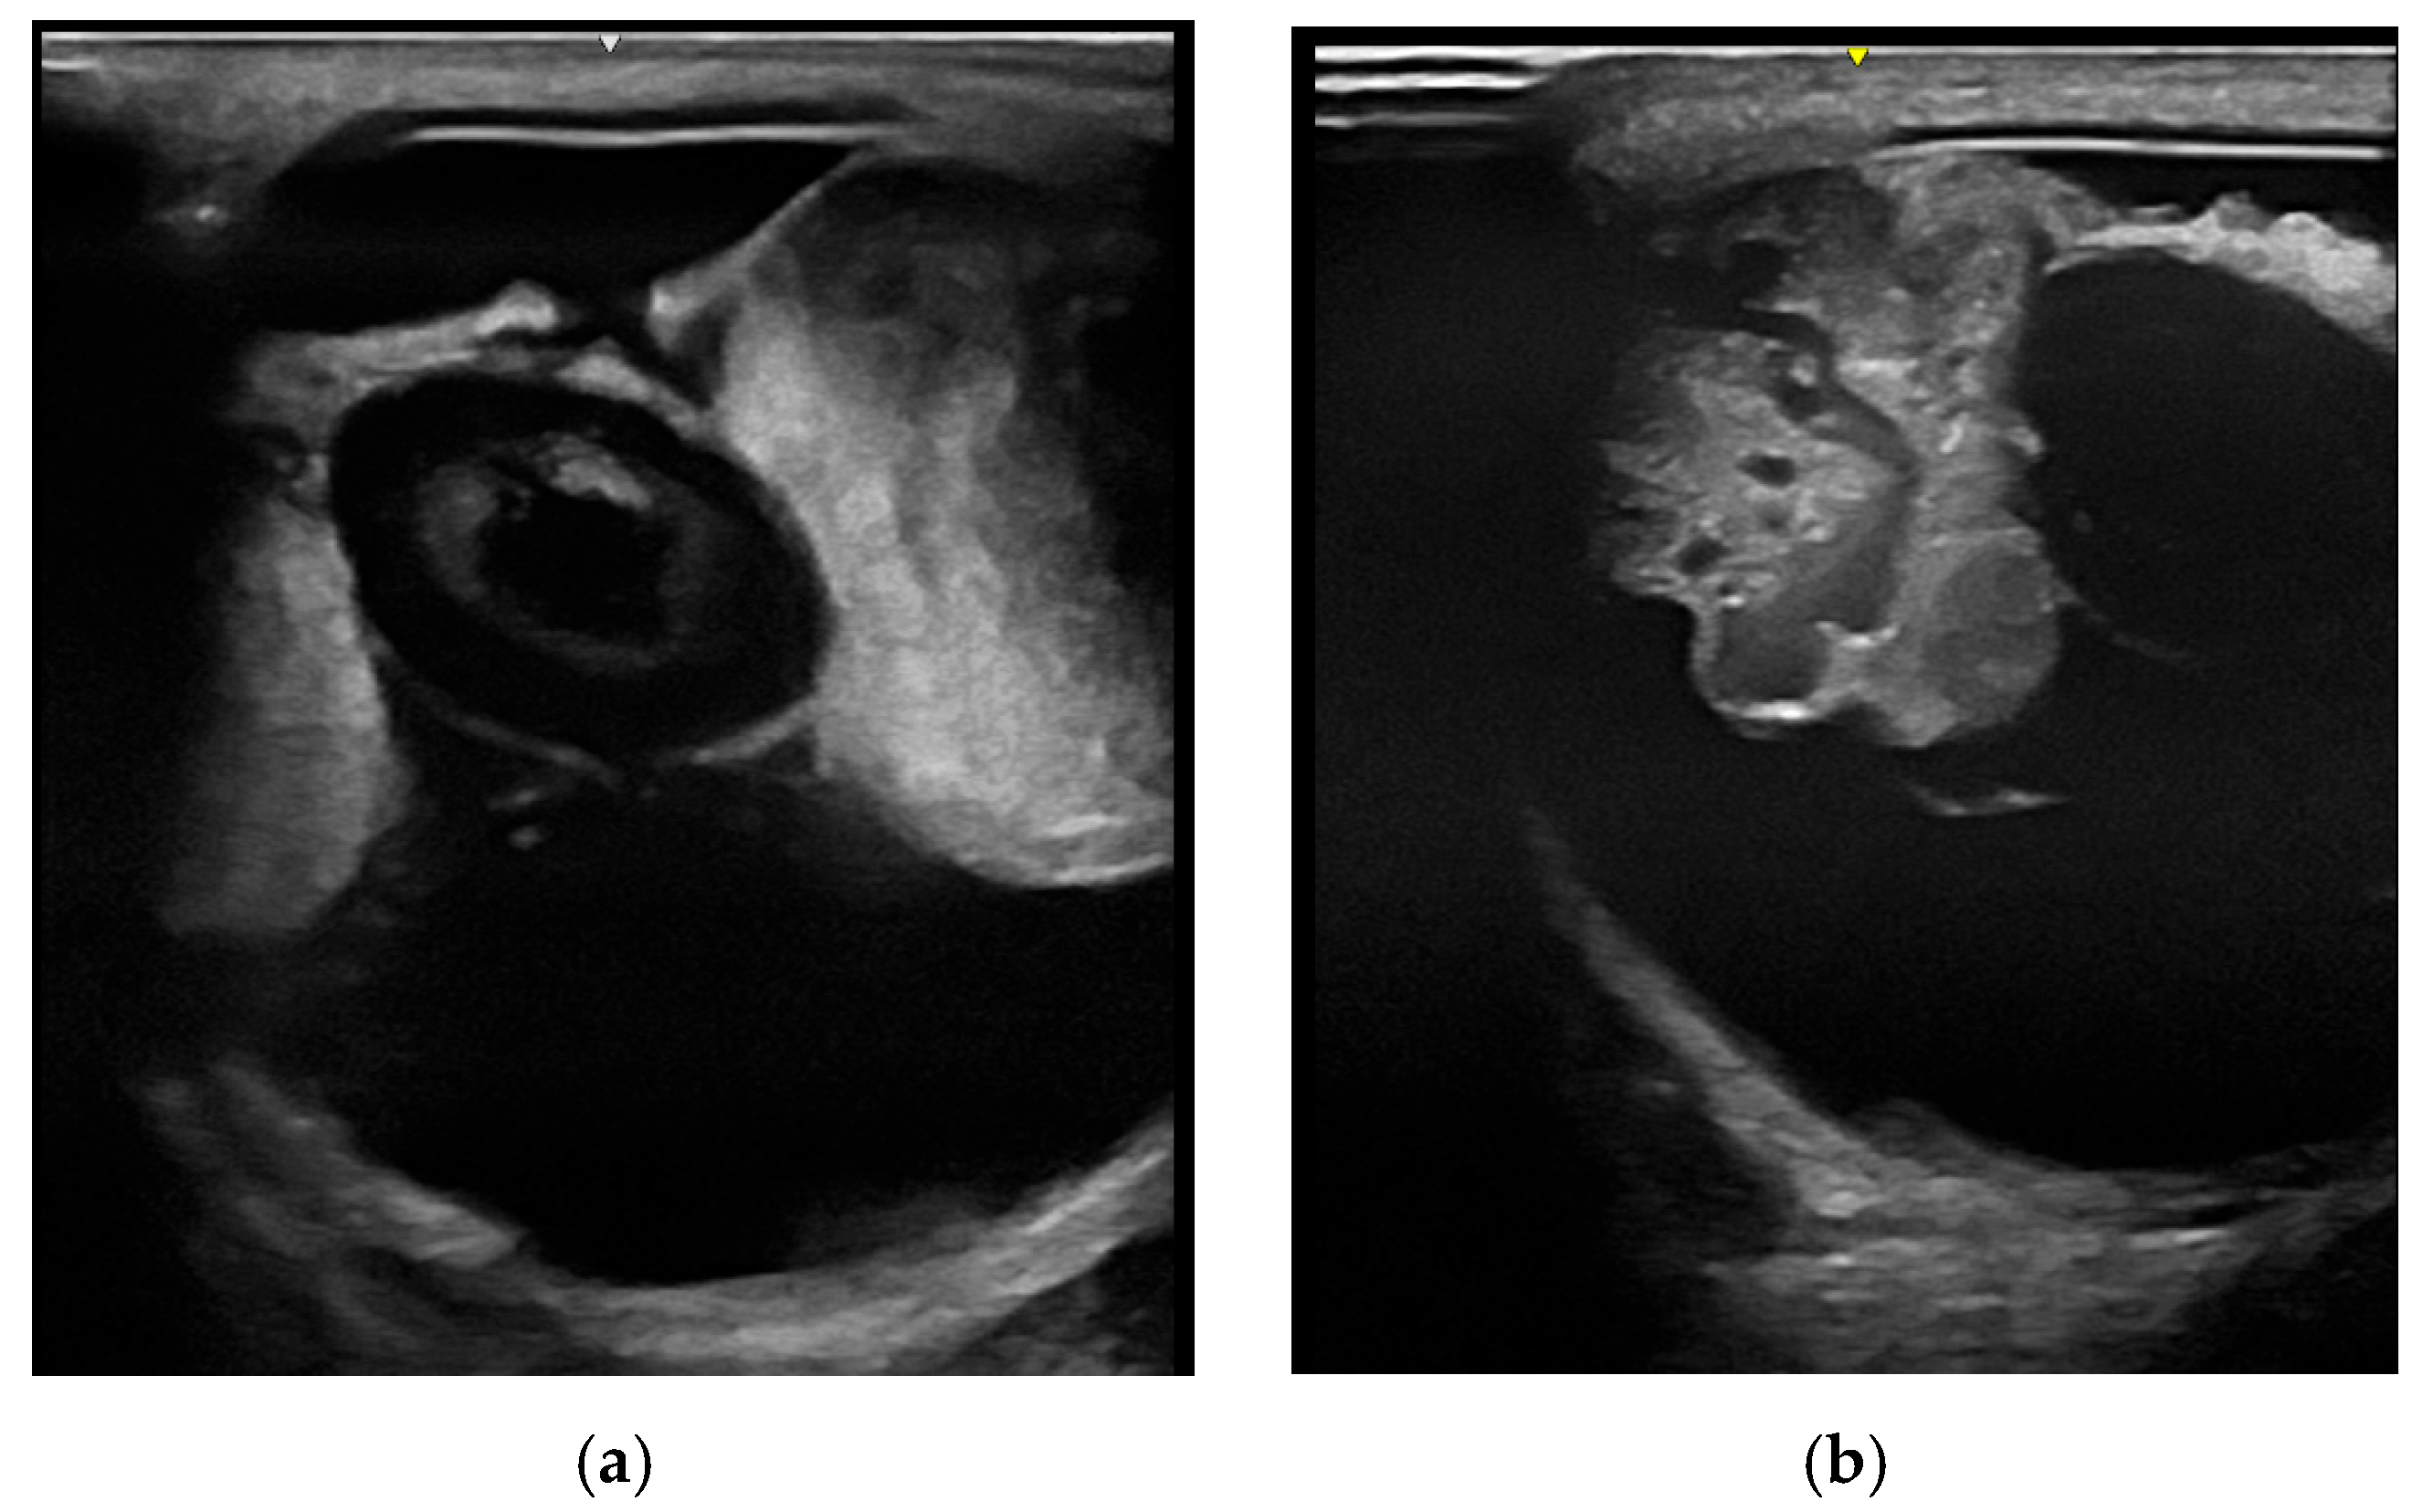

3.2.1. Ultrasonography